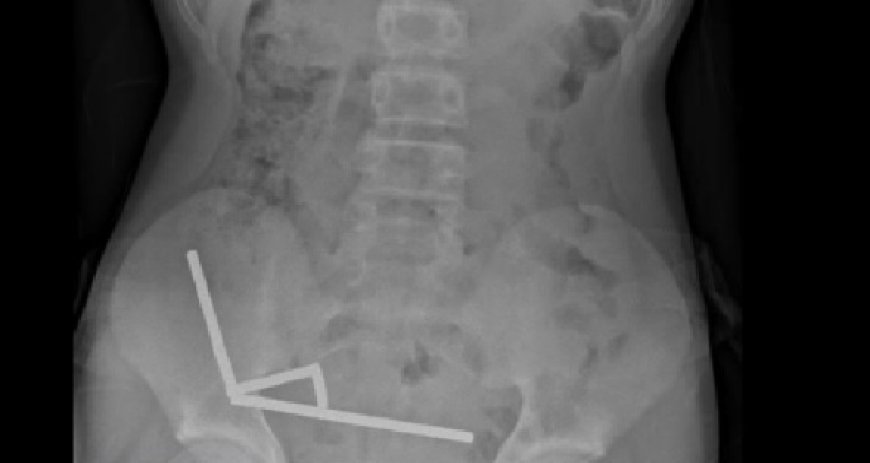

Exames revelaram que os ímãs haviam se agrupado em quatro correntes na parte inferior direita do abdômen, unindo diferentes seções do intestino com sua força magnética, segundo o relatório, que observou que algumas imagens foram distorcidas pelos ímãs. Os médicos então procederam com uma cirurgia exploratória.